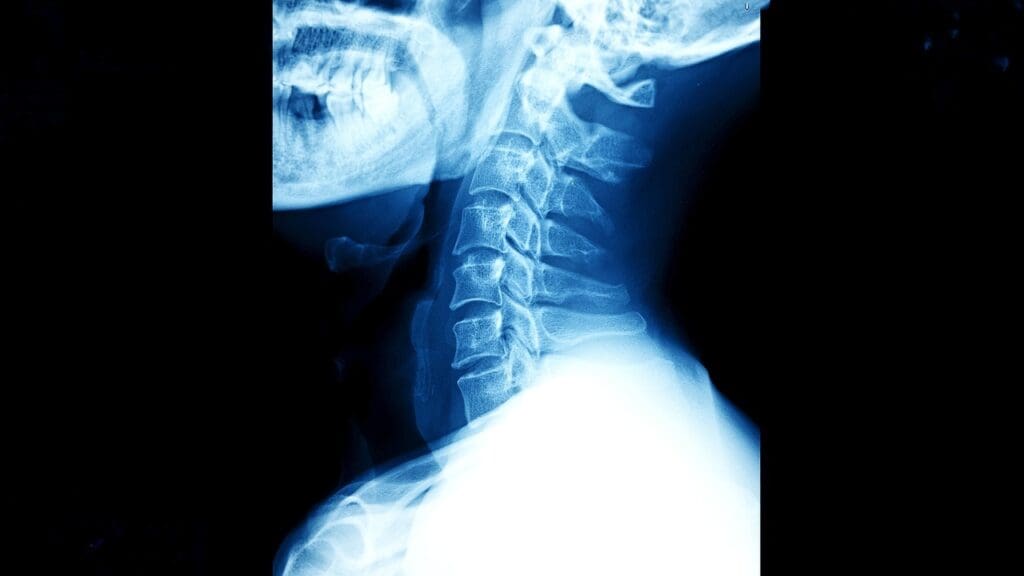

Going through surgery can be scary, even more so for a complex procedure like Anterior Cervical Disc Fusion (ACDF). As a top healthcare provider, we want to reassure you. ACDF is a proven and effective treatment for many cervical spine issues.

ACDF is a surgery for problems like degenerative disc disease and herniated discs. It also fixes instability in the cervical spine. Recent stats show ACDF is used in over 61% of cervical spine surgeries. This makes it a common and trusted option for those with these issues.

ACDF stands for Anterior Cervical Discectomy and Fusion. It’s a surgery to treat neck pain and other symptoms from cervical spine problems. ACDF spine fusion mainly helps with degenerative disc disease, herniated discs, and spine instability. It removes the bad disc and fuses the vertebrae to stabilize the spine, reduce pain, and enhance life quality.

The ACDF cervical spine surgery term is complex. “Anterior” means the surgery is done from the front. “Cervical” points to the neck area treated. “Discectomy” is the removal of the damaged disc. And “Fusion” is the joining of two vertebrae to stabilize the spine. This surgery shows the progress in spinal surgery, providing a good option for certain cervical spine conditions.